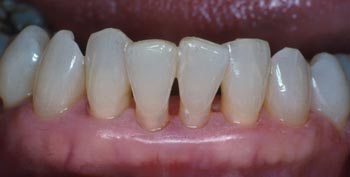

La férula terminada es delgada, confortable y estética.

Con la ferula lingual de composite reforzada con Ribbond terminada, el paso final es la verificación de la oclusión, comprobando que no ha habido nigún cambio y que el paciente acepta la estética.

La férula acabada proporciona estabilidad a los dientes y mayor funcionalidad sin aumentar el volumen.

Con la ferula lingual de composite reforzada con Ribbond terminada, el paso final es la verificación de la oclusión, comprobando que no ha habido nigún cambio y que el paciente acepta la estética. La férula acabada proporciona estabilidad a los dientes y mayor funcionalidad sin aumentar el volumen.

Observese que se dió nueva forma a la superficie mesial del incisivo central para mejorar la estética en comparación con el incisivo lateral adyacente. La paciente comentó que podía volver a comer con los dientes delanteros sin ningún dolor. Los dientes no presentan ninguna movilidad.

La férula Ribbond completa proporciona soporte y estabilización de los dientes anteriores inferiores comprometidos periodontalmente.

La férula finalizada ha estabilizado y ferulizado los dientes con un mínimo grosor. El paciente confirma que puede comer cómodamente con los dientes ferulizados.